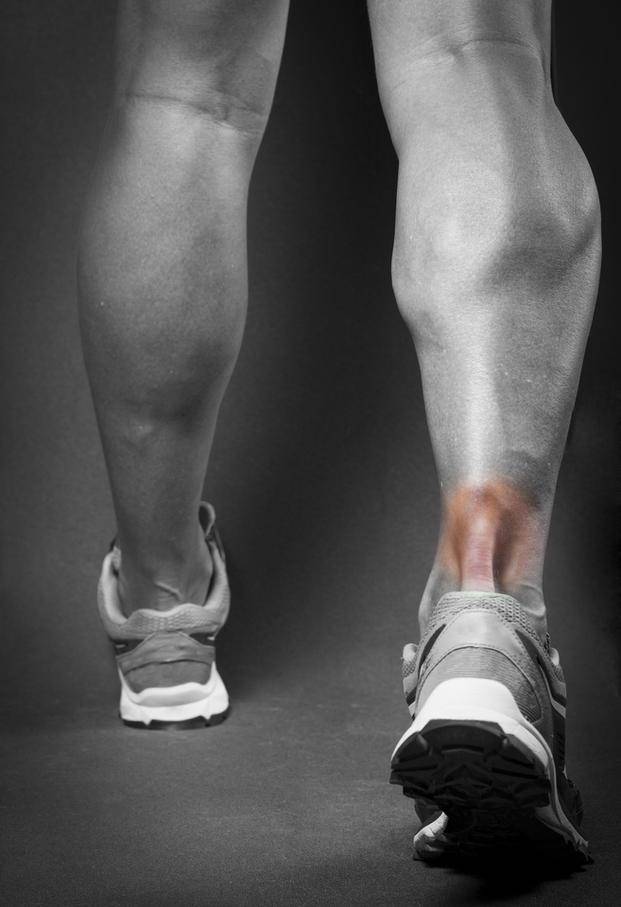

Electrólisis percutánea

POR | DR. NORBERTO FURMAN Doctor en kinesiologIa y fisiatrIa

La lesiones de tendones y ligamentos han torturado al ser humano en todas las épocas, sobretodo en la actualidad en donde el pobre hombre estresado pretende canalizar sus tensiones a través del deporte y la gimnasia. Esa tan ansiada válvula de escape se puede ver truncada por un simple y tal vez diminuto ligamento o tendón. Basta un movimiento mal realizado o una sobrecarga en la actividad deportiva para que surja la lesión e impida que la persona continúe con su rutina y lo que es peor, por mucho tiempo.

Hasta ahora las armas que contaba la medicina deportiva eran las infiltraciones y la fisioterapia, terapias que demandaban demasiado esfuerzo y tiempo para satisfacer la ansiedad del que sufría, además las infiltraciones con corticoides tienen un límite de aplicaciones.

Los tendones al momento de lastimarse son invadidos por un tejido de cicatrización, algo así como si uno volcara un tarro de pegamento que lo envuelve, endurece e impide que el tendón cumpla su función de sostener y estabilizar una articulación; esa fibrosis provoca un intenso dolor y falta de elasticidad.

Actualmente y luego de muchas investigaciones que se iniciaron en España, se comenzó a trabajar con corrientes eléctricas sobre las lesiones pero en una forma distinta a la que se usualmente se trabajaba en la kinesiología tradicional; la idea era llegar a la lesión misma con una aguja y aplicar una determinada corriente eléctrica y pasar la barrera de la piel.

A esta nueva forma de tratar las tendinitis se la llamó electrolisis percutánea y consistía en ubicar los puntos lesionados ya sea palpando o con una ecografía, colocar una aguja de acupuntura y hacer pasar una corriente galvánica; esta electricidad combinada con las sales y los líquidos contenidos en los tejidos, provocaba una reacción química y daba como resultado el llamado hidróxido de sodio, una sustancia cáustica que destruye instantáneamente el tejido de cicatrización que ha invadido el tendón a la vez que inicia una reacción inflamatoria que en pocas horas repara la afección. La reparación, en definitiva, se logra cuando el tendón se defiende de la agresión provocada intencionalmente. El paciente debe esperar 48 horas para poner hielo o tomar algún medicamento para no cortar la inflamación provocada en el tratamiento y que será la que cure el problema. Esta nueva terapia destruye el tejido fibrótico a la vez que repara la lesión devolviendo funcionalidad al tendón.

La cantidad de aplicaciones que se recomiendan son entre 1 y 5 sesiones y se puede aplicar en afecciones como tendinitis de todo tipo, codo de tenista, trocanteritis, fascitis plantar, lesiones de rodilla, pubalgias, dedo en resorte, desgarros musculares, lesiones de hombro y del tendón Aquiles.

Entendamos que día a día se descubren nuevas y mejores propiedades de la electrolisis percutánea así como también se experimenta sobre otras enfermedades de los tejidos blandos que rodean nuestras articulaciones, parece ser que la tortura de soportar el dolor en muchas de las lesiones crónicas deportivas y no tan deportivas va llegando a su fin, la ciencia, la electroterapia y la tenacidad de los profesionales del arte del curar lo están logrando.